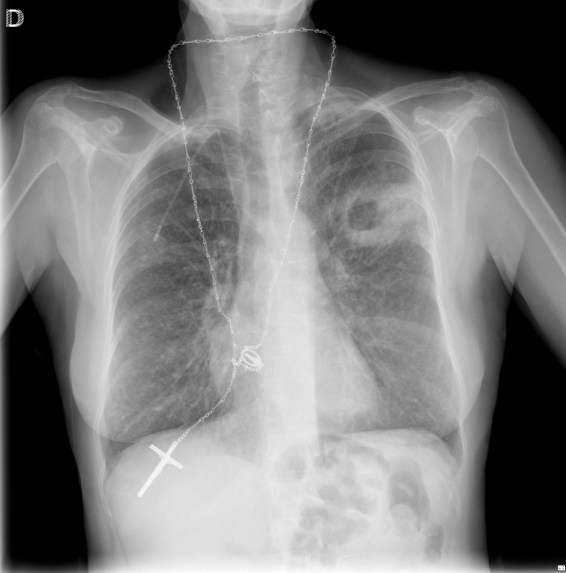

Empecemos, ¿qué ves?

- Comprobar que la placa está bien centrada e inspirada (6 arcos costales anteriores ó 9 posteriores).

- Abdomen y Diafragma

- Partes blandas y estructura ósea.

- Mediastino con silueta cardiaca.

- Parénquimas pulmonares (por separado)

- Comparar un pulmón con otro.

Seguir esta sistemática, dejando el pulmón para el final no nos olvidaremos de lo más importante.

Regla: Acaso Tiene Mucha Patología Pulmonar (Abdomen, Tejidos blandos y hueso, Mediastino, Pulmón por separado, Pulmón bilateral)

Nota: ¡¡¡No olvidar la placa lateral!!! La regla a seguir es la misma. Leer abdomen y diafragma, examinar parte posterior, tejidos blandos y subir por la columna; tráquea y descender por mediastino. Finalmente pulmones.

Solución: Es un estudio Normal. Silueta cardiomediastínica y parénquimas pulmonares sin alteraciones significativas.